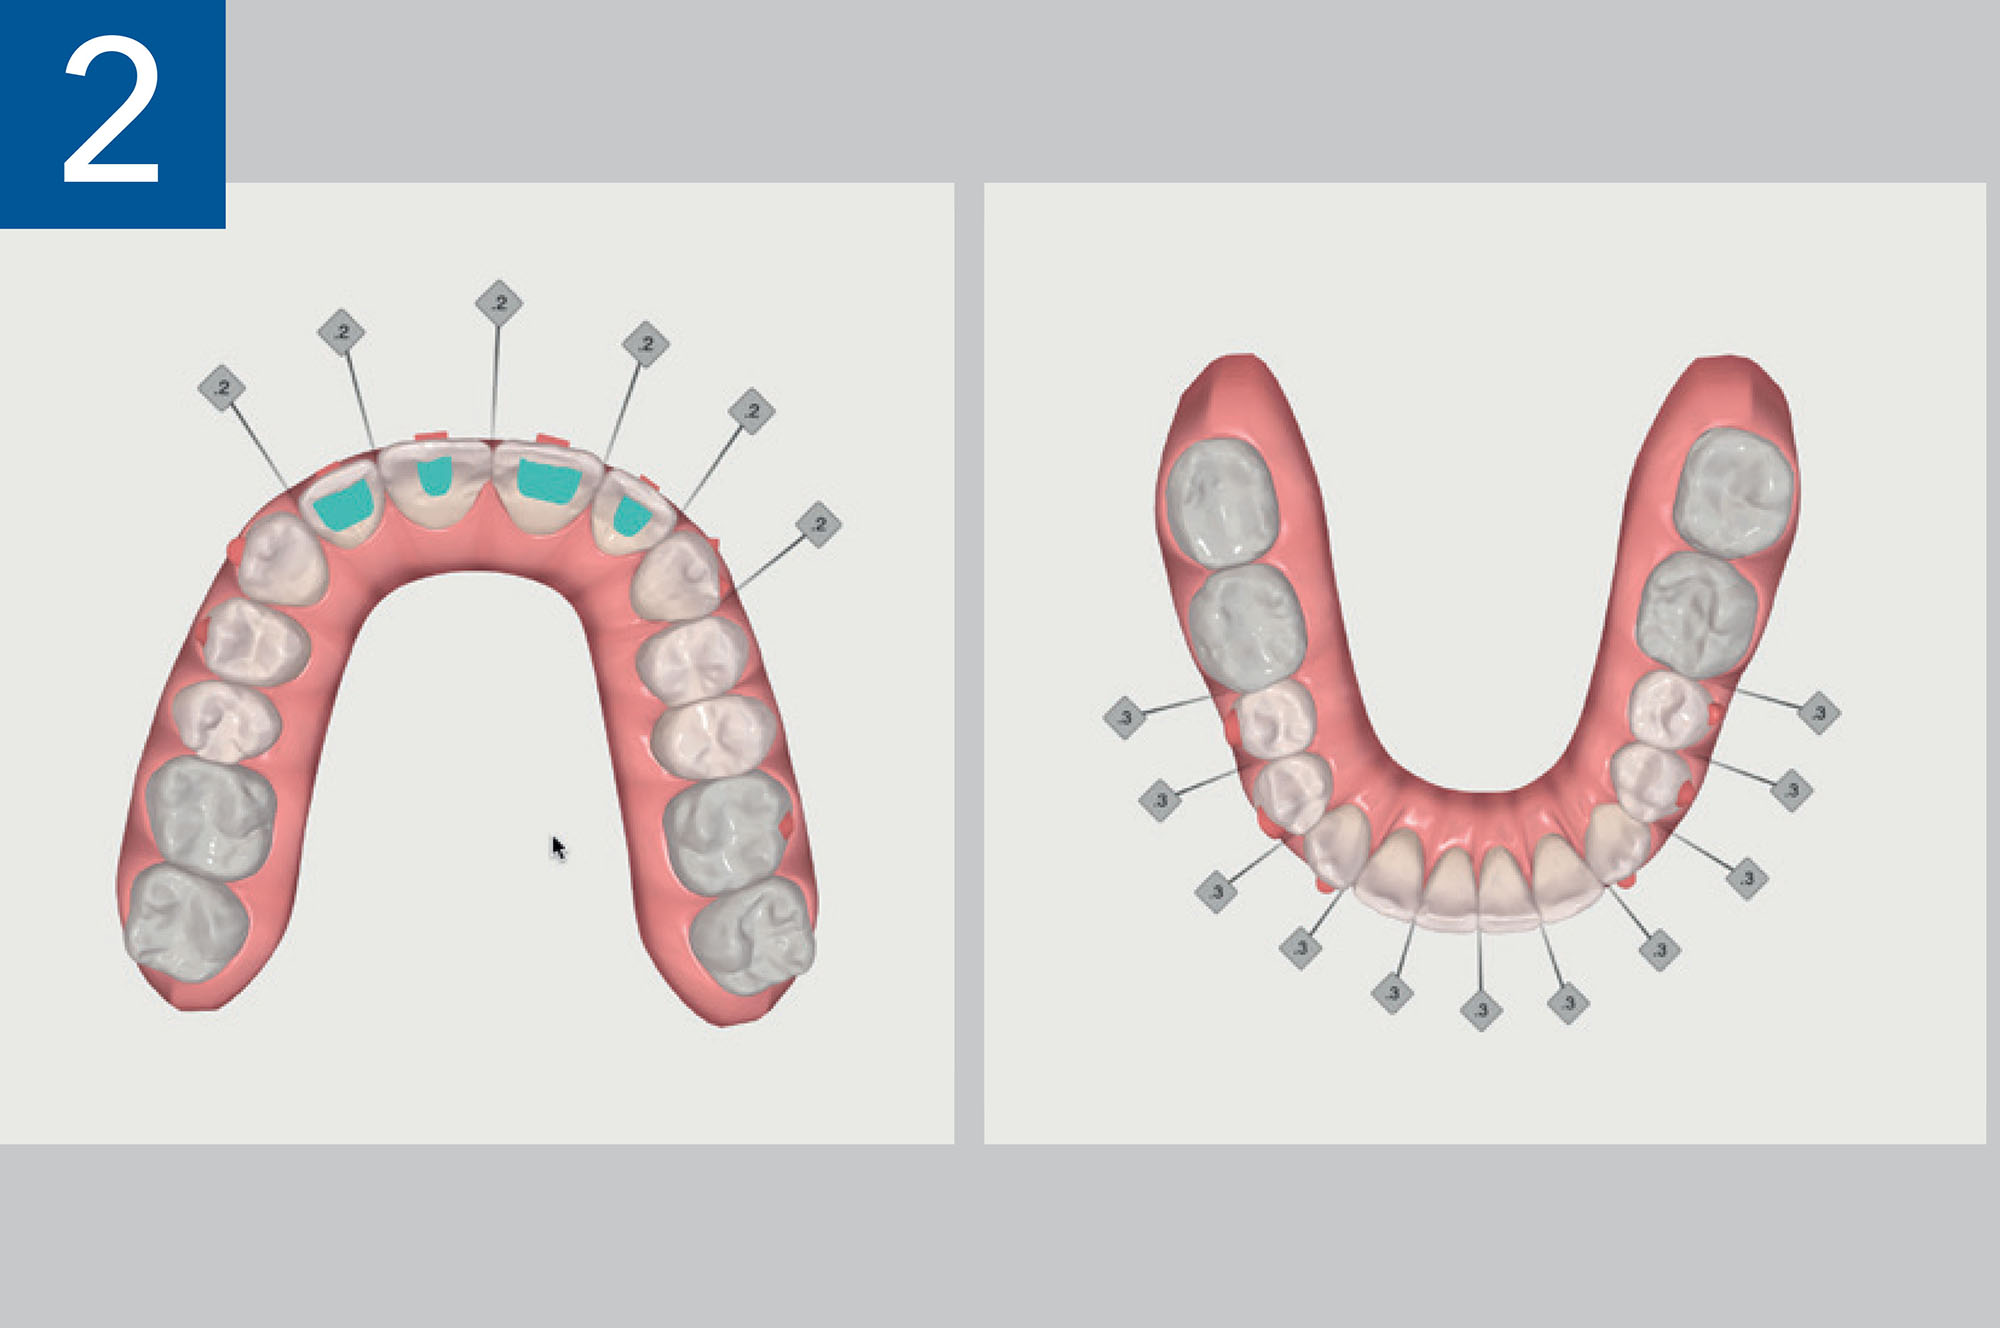

Pianificazione ClinCheck (Align Technology Inc., Tempe, AZ, USA) in cui è evidente la significativa quota di stripping richiesta.

Pianificazione ClinCheck (Align Technology Inc., Tempe, AZ, USA) in cui è evidente la significativa quota di stripping richiesta.